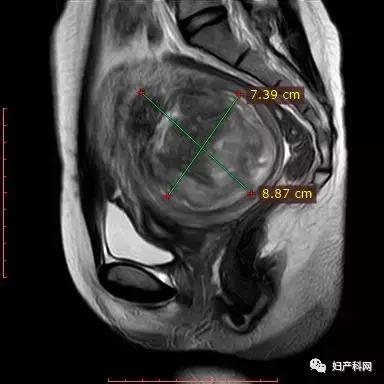

2016年7月因多发性子宫肌瘤,于当地医院开腹剥除子宫肌瘤,术中剥除较大者肌瘤约13cm,次大者约7cm,术后病例:子宫肌瘤,细胞较丰富。术后1年复查超声发现子宫肌瘤复发,大小约1cm。术后月经规律,周期30天,经期3-5天,经量明显减少,痛经(-)。2018年10月就诊,超声提示子宫肌瘤大小5.5×4.4×5.5cm,嘱随访。2019年5月再次就诊,复查超声提示子宫肌瘤9.2×7.5×7.0cm,内见部分变性改变。

这个患者第一次来找我们就诊时,虽然术后复发的肌瘤有5cm左右了,但没有任何的症状,近期也没有生育的计划,所以我给她的建议是先继续观察,等到有生育需求的时候,我们再评估当时的子宫肌瘤是否会影响生育再进行处理。今年6月患者再次来就诊时,根据超声发现子宫肌瘤长大了不少,最大径线已经9cm了,因为曾经有过一次开腹手术的体验,患者自身比较焦虑。考虑她子宫肌瘤生长的速度比较快,继续观察的话,很有可能会加大处理的难度,同时因为MRI提示子宫肌瘤为T2等或高信号,进行完全无创的磁波治疗会比较困难,我给她选择了经皮的微波治疗。